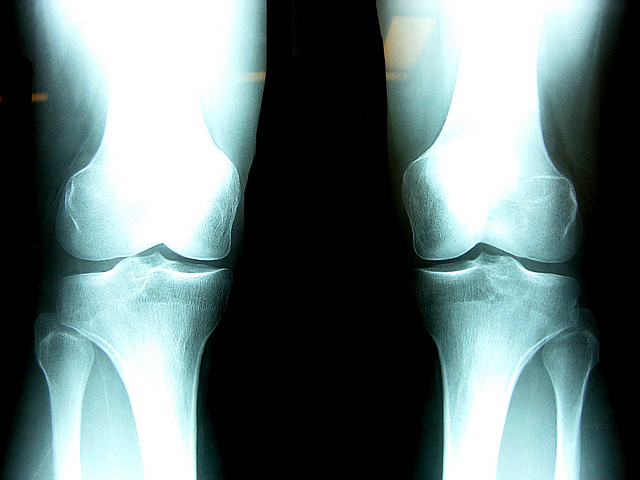

Joint Replacement

Is it right for you?

If you experience pain in any of your joints due to physical activities such as walking, running, and climbing stairs, it may be time to have a Rothman Orthopaedic Institute specialists diagnose your case. Joint replacement may be the answer for you. When simply sitting in a favorite chair or sleeping in your bed causes enough pain to wake you or make your life extremely uncomfortable, joint replacement may be able to get you back to an active lifestyle with less pain.